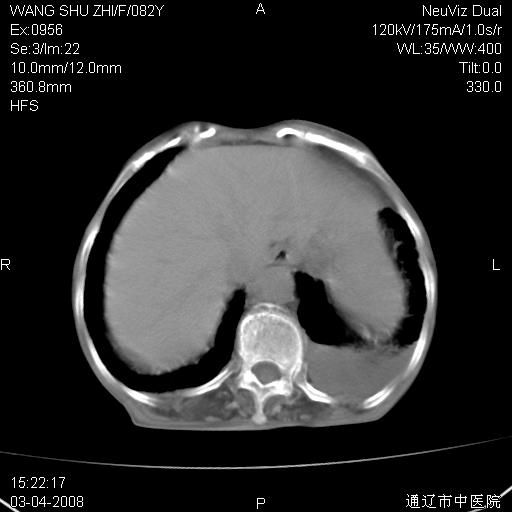

该患者为女性,82岁,既往肺心病、心衰病史。上纵隔影增宽,是否为畸形扩张的血管呢?因该患者年龄太大,又有较严重心脏病,故不适宜做增强检查。

中纵隔肿块最多见是淋巴瘤,而且以hd为多见,呈侵袭性生长,纵隔脂肪间隙消失,再加上心包和双侧胸腔积液,考虑为淋巴瘤(hd)应该说比较准确的。至于说是畸形的血管可能性小,因为畸形血管周围脂肪间隙应该存在。

纵隔淋巴结转移或淋巴瘤;双侧胸腔积液,心包积液。肺窗呢?

左侧腋窝及纵隔内见多个肿大淋巴结影,左侧少量胸腔积液,心包积液,支持淋巴瘤可能性大,不除外淋巴结转移。

纵隔淋巴结转移或淋巴瘤;双侧胸腔积液,心包积液,建议进一步检查。